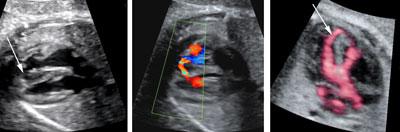

Pulmonary atresia with intact ventricular septum

Legend:Pulmonary atresia with intact ventricular septum: the right ventricle is small, there is significant tricuspid regurgitation, there is no flow across the pulmonary vale, and there is streaming of flow into the pulmonary artery as a consequence of retrograde perfusion through the ductus arteriosus

Reference(s):Todros T, Paladini D, Chiappa E, Russo MG, Gaglioti P, Pacileo G, Cau MA, Martinelli P. Pulmonary stenosis and atresia with intact ventricular septum during prenatal life. Ultrasound Obstet Gynecol 2003;21(3):228–33. PubMed PMID: 12666215.